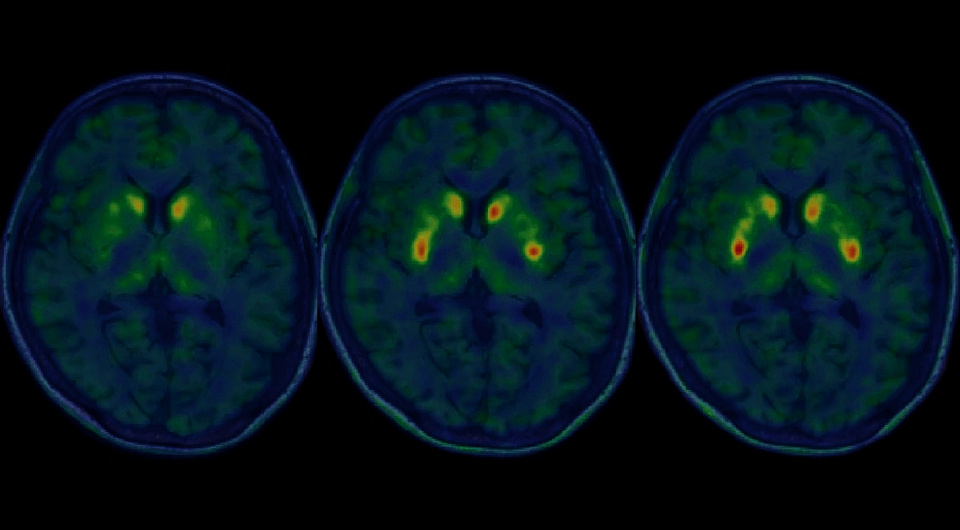

Nobukatsu Sawamoto et al. / Nature, 2025

Основанием для одобрения стали результаты открытых нерандомизированных испытаний фазы I/II. В ходе них семь пациентов (возраст 50–69 лет) с болезнью Паркинсона получили двустороннюю трансплантацию рагунепроцела. Серьезных побочных эффектов не было, как и избыточного роста трансплантатов. У четырех из шести участников, включенных в анализ эффективности, наблюдалось значительное улучшение счета OFF и у пяти — счета ON шкалы MDS-UPDRS, у четырех наблюдалось улучшение стадии заболевания по шкале Хён — Яра.